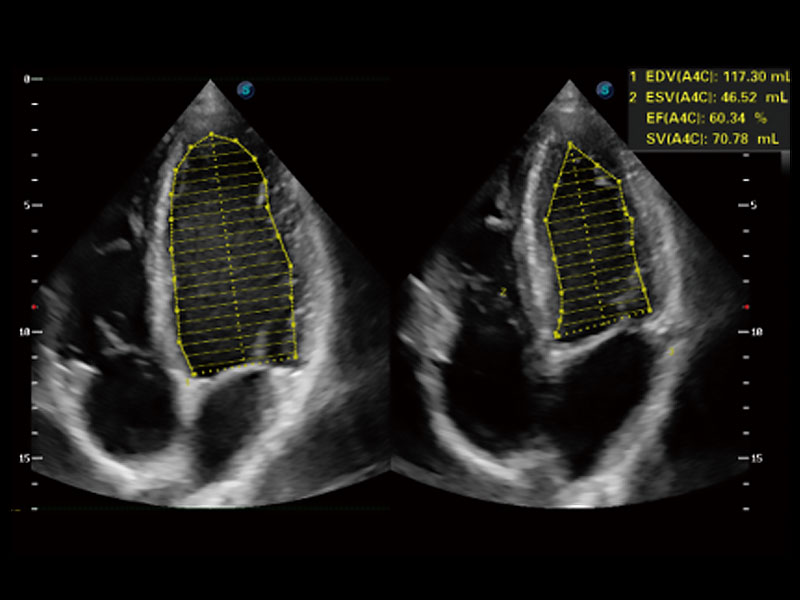

能够基于左心室壁追踪和辛普森法,自动计算射血分数,支持多个可移动点描迹,与手动测量相比,极大节省了动物医生的时间和精力。